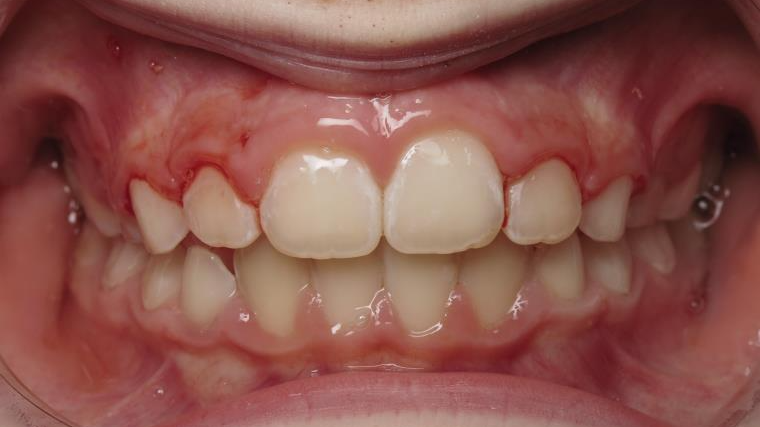

sectionnel multibagues

surveillance évolution de la dentition pendant 4 ans

bilan début fin de traitement